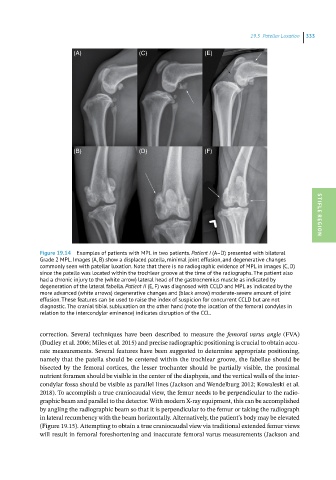

Figure 19.14 Examples of patients with MPL in two patients. Patient I (A–D) presented with bilateral STIFLE REGION

Grade 2 MPL. Images (A, B) show a displaced patella, minimal joint effusion, and degenerative changes

commonly seen with patellar luxation. Note that there is no radiographic evidence of MPL in images (C, D)

since the patella was located within the trochlear groove at the time of the radiographs. The patient also

had a chronic injury to the (white arrow) lateral head of the gastrocnemius muscle as indicated by

degeneration of the lateral fabella. Patient II (E, F) was diagnosed with CCLD and MPL as indicated by the

more advanced (white arrows) degenerative changes and (black arrow) moderate-severe amount of joint

effusion. These features can be used to raise the index of suspicion for concurrent CCLD but are not

diagnostic. The cranial tibial subluxation on the other hand (note the location of the femoral condyles in

relation to the intercondylar eminence) indicates disruption of the CCL.